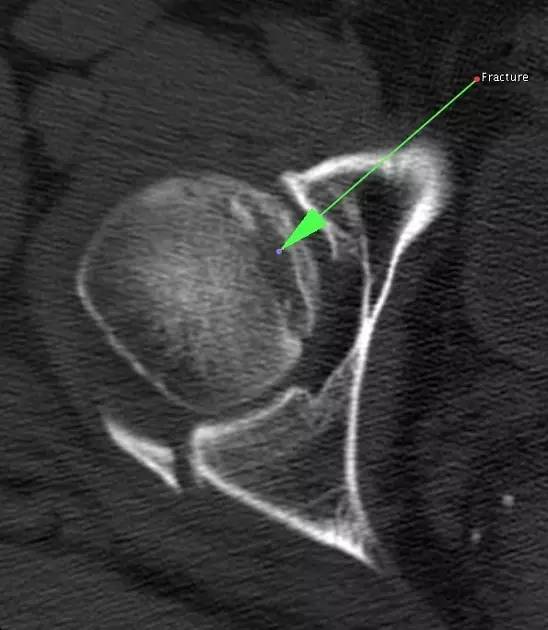

11. Bumper 骨折(保险杆骨折)

是汽车保险杠撞击膝关节外侧,导致的胫骨平台粉碎性骨折,伴有软骨面挫裂和腓骨头骨折。初诊,X 线上正侧位很容易忽略平台的粉碎性,CT 平扫及重建可明确伤情,MRI 可了解副韧带及叉韧带情况。